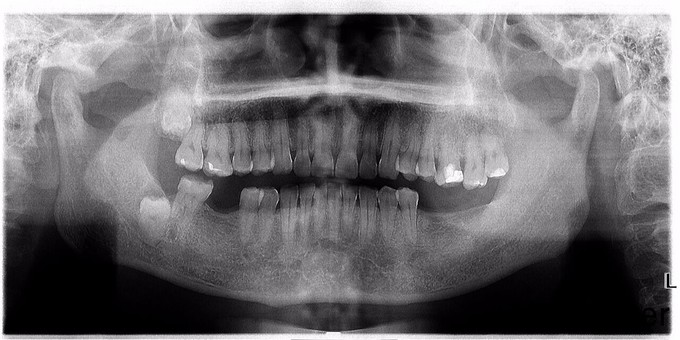

1105垂直阻生智齿的拔除光3

垂直阻生齿

垂直阻生

1107低位垂直阻生智齿的拔除光9